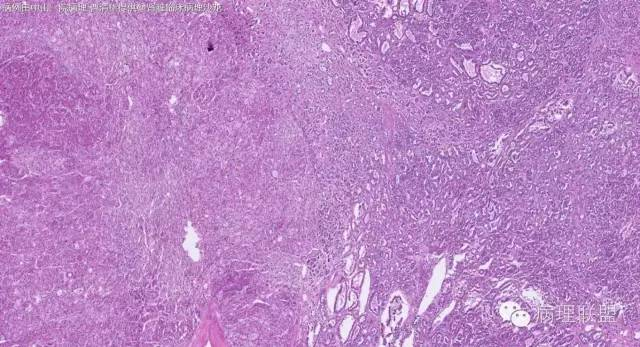

女性,50岁,肾上腺肿物(影像及手术均确认肿物位于肾上腺,界限清楚)。血压升高。(病例由 中山一院病理 曹清华提供,致谢!)

伴假腺样结构的肾上腺皮质腺瘤,合并髓脂肪瘤

从肿瘤的位置及镜下与肾上腺皮质的关系看,应该像是皮质来源肿瘤。假腺样结构的皮质腺瘤没有见过,似乎文献也还没查到。另外inhibina, melanA, syn均阴性(肿瘤旁正常皮质阳)感觉有点迷惑。。。请老师指教,有相关文献么?@武警嘉兴医院 周泉

假腺样是细胞粘附性差了导致。往往可以伴随黏液成分,组化上这几个抗体应该至少会有灶性阳性。